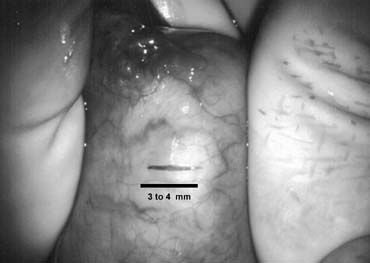

Bilateral 1-cm transverse scrotal incisions provide good exposure with a minimum of scrotal skin bleeding (Fig. 1). Alternatively, a single vertical incision in the median raphe may be employed. Use of loupes or an operating microscope allows ready identification of a relatively avascular area on the tunica albuginia where an incision may be made. A 3- to 4-mm incision is made in the tunica albuginea with a 15-degree microknife (Fig. 2). A pea-size sample of seminiferous tubules is excised with razor-sharp iris scissors (Fig. 3). When handling testis biopsy material for permanent fixation, it is important to avoid tissue traumatization by forcep handling in any way as this may distort the testicular architecture.

Fig. 2. A 3- to 4-mm incision is made on the tunica albuginia, avoiding major crossing vessels.